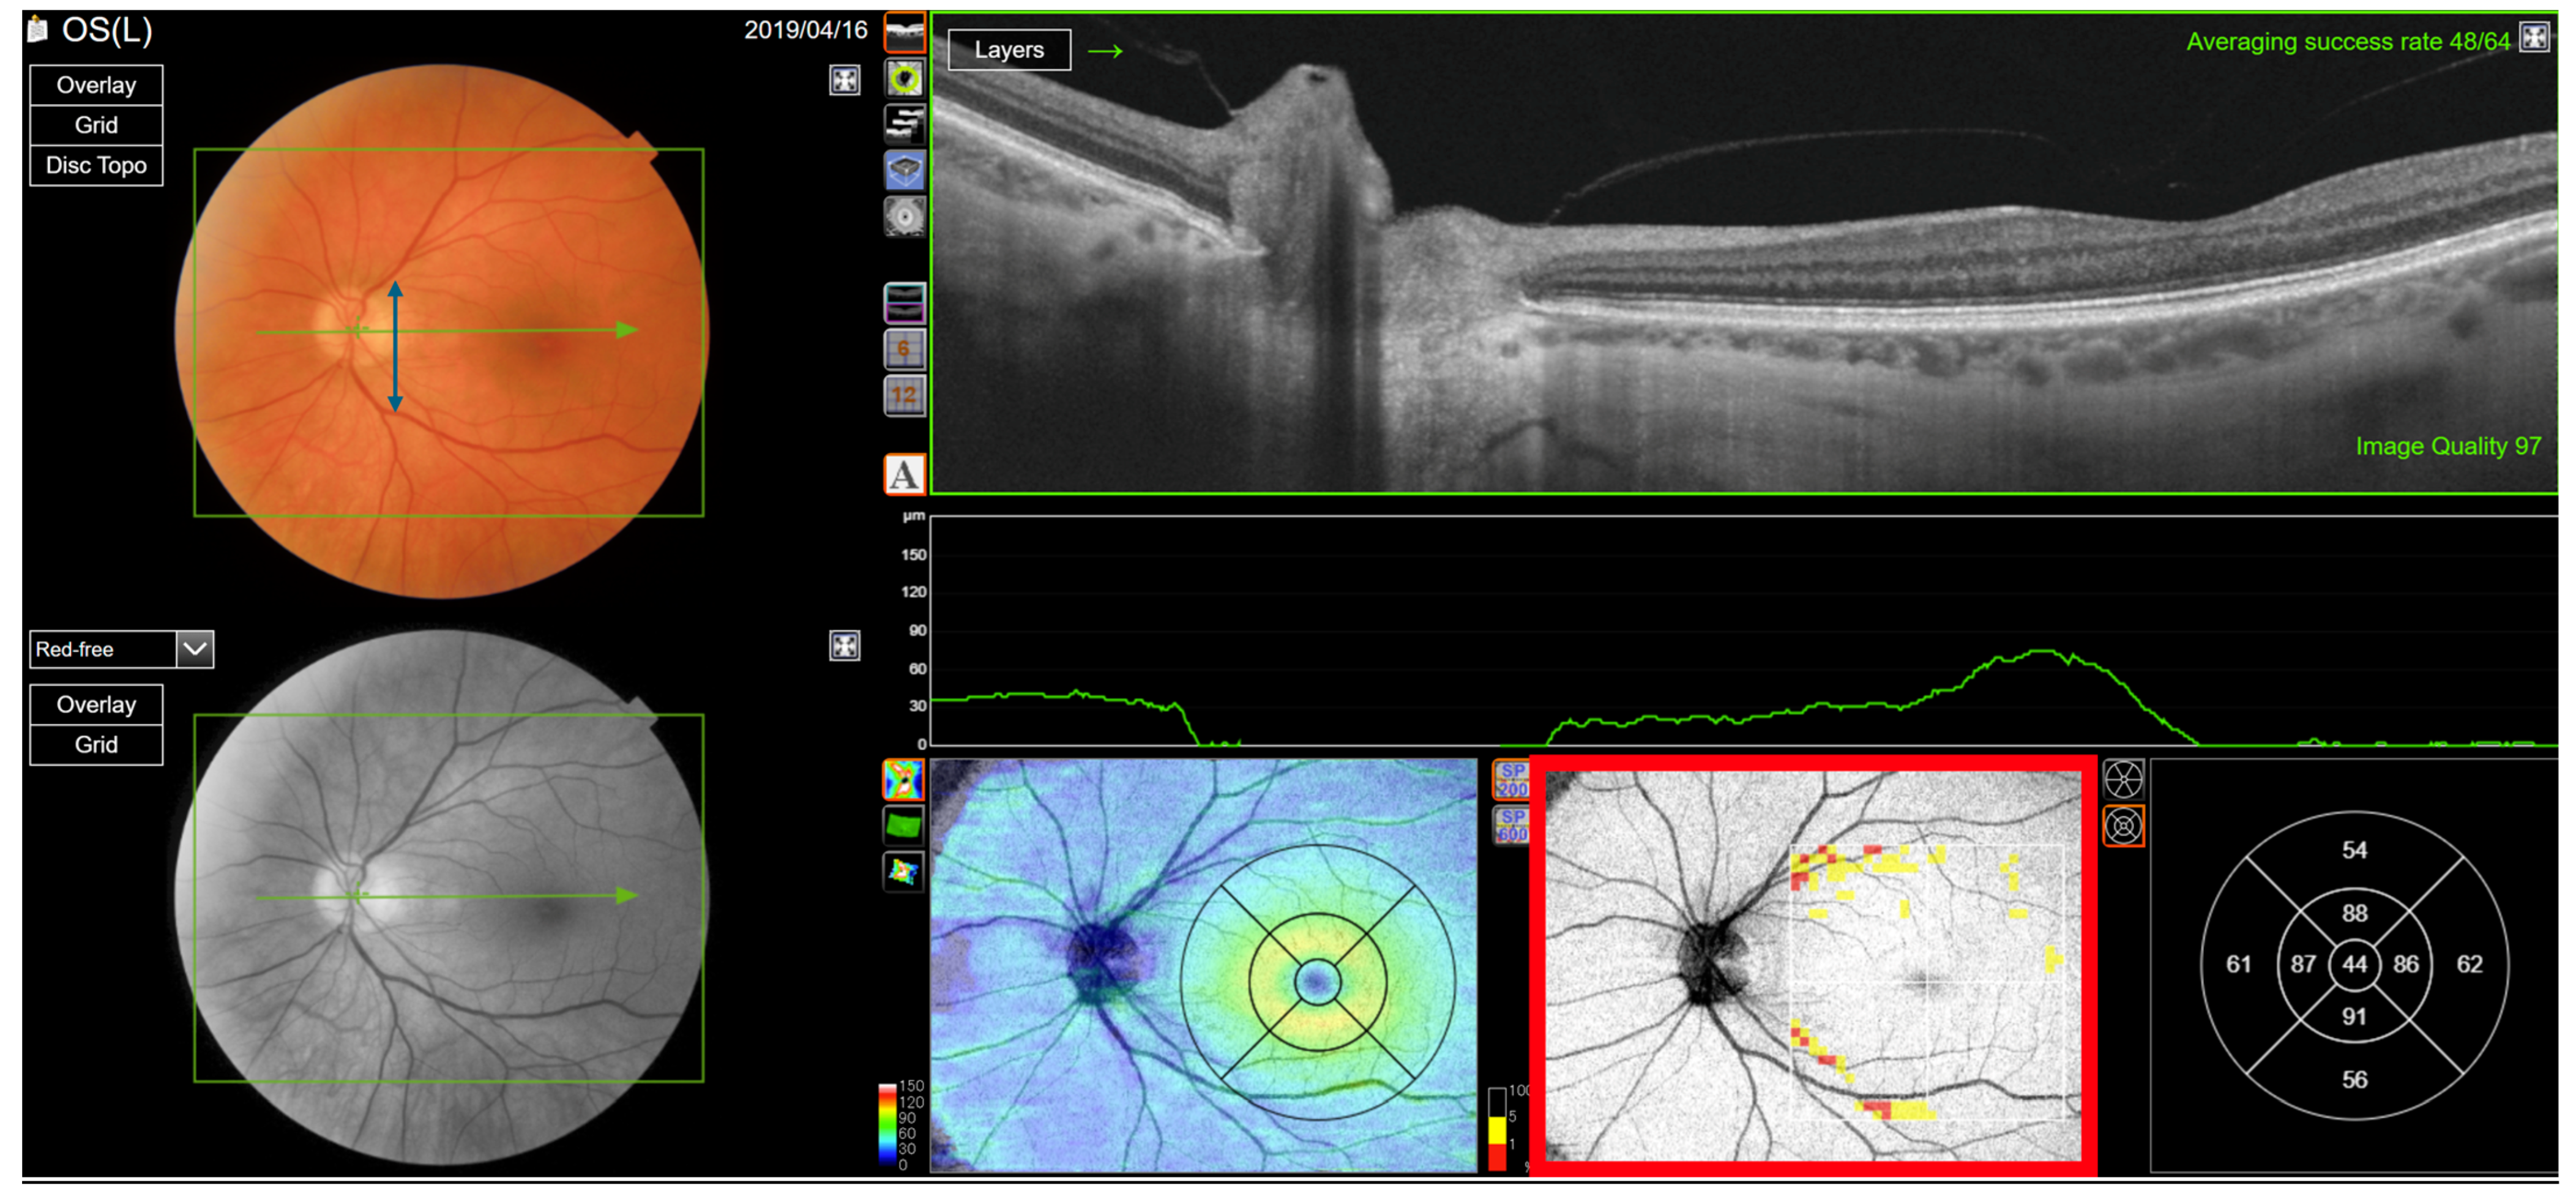

Figure 5. Type 2 RNFL thickness deficit alerts from a healthy left eye. The angle between the temporal nerve fibre ridges is wide (black double-headed arrow) compared to the template (green double-headed arrow). This results in nominal thickness deficits (red arrows) superior and inferior of the disc, that happen to be balanced by thick adjacent nerve fibre sectors (B). The peripapillary retinal nerve fibre layer (RNFL (A)) and its thickness curve in ((B) black, blue and purple); N, nasal; S, superior; T, temporal; I, inferior quadrants; 0 degrees representing the temporal horizontal meridian. Red vertical lines (B) show the location of the superior and inferior arcuate trunk vessels. The peaks of the superior and inferior arcuate nerve fibre ridges or the template or reference curve are close to the innermost red lines. An en face slab of the inner retina shows the RNFL analysis (C), RNFL thickness map (D), and RNFL sector analysis (E). The macular ganglion cell and inner plexiform layer (GC-IPL) thickness map is shown on (F). The RNFL probability map is shown on (G) and the GC-IPL probability map on (H). In (G+H) green colour indicates that thickness is within the best 95% of healthy subjects at a given test location. For other colours, see colour bar next to (G+H). VF, visual field. GCL+ above = GC-IPL.

The Type (2) Wide RNFL angle, found in 81 eyes (13%), is an alert that arises from the temporal nerve fibre ridges being separated by a large angular distance compared to the reference (Figure 5, panels B and D). The alerts are comparable to Type 1 defects, but they are located closer to the fovea.